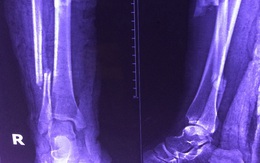

Bệnh viện tuyến cuối từ chối, bệnh viện quận ghép xương thành công

TTO - Chị Lê Thị Ngọc D. (39 tuổi, Long An) bị gãy xương cẳng chân phải thành hai đoạn. Do chị D. có thể chết trên bàn mổ vì bệnh tứ chứng Fallot (một loại bệnh tim bẩm sinh nặng) nên một số bệnh viện từ chối mổ.